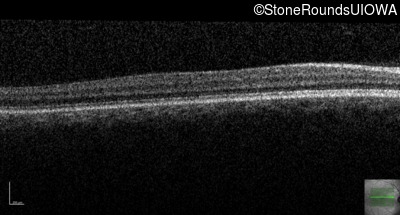

Optical Coherence Tomography - Right - 20/200

Exemplar / OCT Stack

OCT Stack